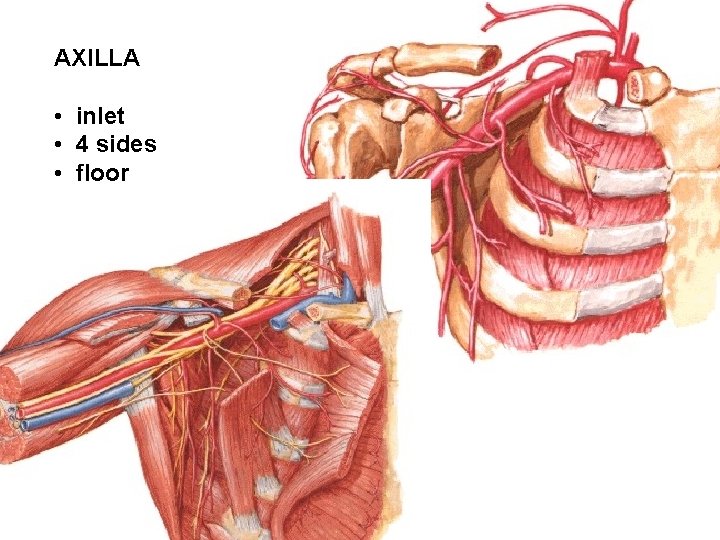

AXILLA • inlet • 4 sides • floor

Anterior wall: m. pectoralis major (n. pectoralis med. et lat. ) m. pectoralis minor (n. pectoralis med. ) m. subclavius (n. subclavius) fascia clavipectoralis a. thoracoacromialis, a. pectoralis sup.

Medial wall: thorax m. serratus ant. (a. thoracica lat. , n. thoracicus longus)

Lateral wall: humerus, m. biceps brachii Posterior wall: m. subscapularis m. teres minor m. teres major

Posterior wall: m. latissimus dorsi – foramen omotricipitale (trilaterum): m. teres minor m. teres major caput longum m. tricipitis A. circumflexa scapulae - foramen humerotricipitale (quadrilaterum): m. teres minor m. teres major caput longum m. tricipitis humerus A. circumflexa humeri post. N. axillaris

Floor: Fascia axillaris Plica axillaris ant. (m. pectoralis major) Plica axillaris post. (m. latissimus dorsi)

Contents: M. biceps brachii M. coracobrachialis

A. axillaris - rr. subscapulares - a. thoracica suprema (superior) - a. thoracoacromialis - r. deltoideus - r. acromialis - rr. pectorales - a. thoracica lateralis - rr. mammarii lat. - a. subscapularis - a. thoracodorsalis - a. circumflexa scapulae - a. circumflexa humeri ant. - a. circumflexa humeri post.